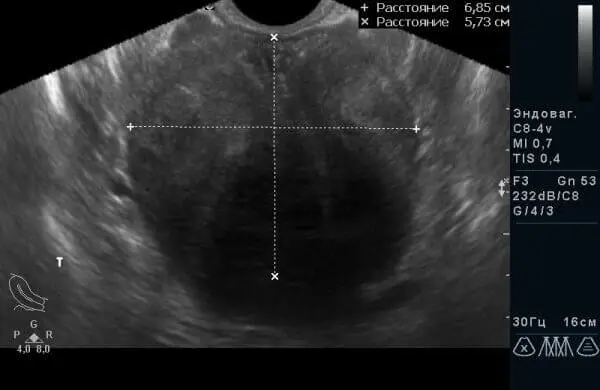

Мал. 3 Той же пацієнт через 14 днів від початку консервативної терапії.